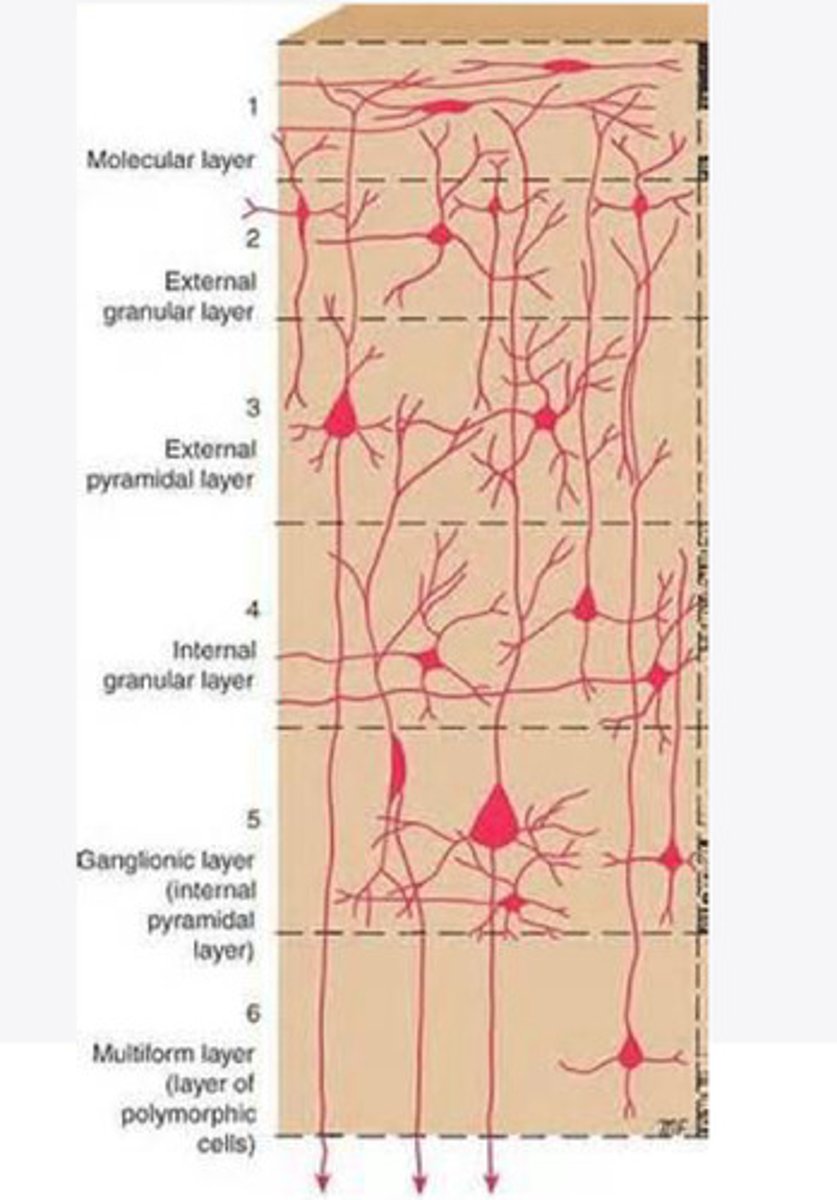

divided into 6 distinct layers, due to varying densities of cell body types within each layer

The cortex of the brain is divided into how many layers? Why is it divided into layers?

Layers of the cortex of the brain pic

2 and 4

What are the layers of the cortex that are associated with input?

3 and 5

What are the layers of the cortex that are associated with output?

molecular layer

What is the name of Layer 1 of the cortex of the brain?

very few cells

Does Layer 1 of the cortex have a lot or few cells?

receives dendrites from internal layers so it may actually function as a coordinating center where layers can communicate action

What does Layer 1 of the cortex do?

1

Every layer sends densities to Layer ____?

1

What layer serves as the "water cooler" of the brain?

external granular layer

What is the name for layer 2 of the cortex of the brain?

receives input from other cortical regions

What is the function of Layer 2 of the Cortex of the brain?

Stellate

What type of cells (stellate/pyramidal) would be most concentrated in Layer 2?

external pyramidal layer

What is the name for layer 3 of the cortex of the brain?

sends output to the other cortical layers

What is the function of Layer 3 of the cortex of the brain?

pyramidal

What type of cells (stellate/pyramidal) would be most concentrated in Layer 3 of the brain?

Layers 2 and 3

What layers are associated with association and commissural fibers?

Layer 3 - axons of cell bodies

Layer 2 - synapse into target areas in Layer 2

What part of the axons is in Layer 2/ in layer 3?

Layer 3 - external pyramidal layer

All axonal cel bodies for association and commissural fibers lie within what layer of the Cortex of the brain?

internal granular

** or called the striate cortex because it is so thick that you can see a line through this layer even in unstrained brain slides

What is the name for the 4th layer of the cortex of the brain?

receives input from the thalamus, geniculocortical layer, and other brainstem areas

What is the function for the 4th layer of the Cortex of the brain?

very thick within the vision, auditory, and somatosensory areas

Is Layer 4 thick or thin within SENSORY areas of the cortex?

Internal pyramidal

What is the name for Layer 5 of the cortex of the brain?

sends axons to the brainstem (corticobulbar) and spinal cord (corticospinal)

What is the function of Layer 5 of the cortex of the brain?

in motor areas of the cortex?

Where is layer 5 very thick in the brain?

the frontal lobe -- very motor heavy

What lobe of the brain will have a thick layer 5 of the cortex of the brain?

the multiform layer

What is the name of layer 6 of the cortex of the brain?

-sends axons back to the thalamus through corticogeniculate fibers

-modulates what information the thalamus sends to the cortex to control the strength of the signal received and modulate what you pay attention to

What is the function of layer 6 of the cortex of the brain?

no

Is layer 6 a motor layer?